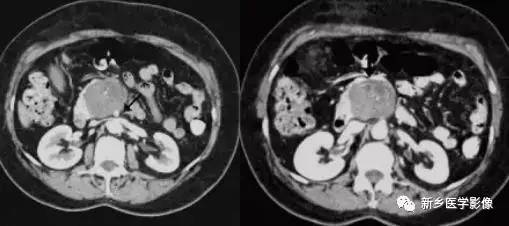

四、胰腺转移瘤

胰腺转移瘤在临床上较为少见, 1000 例恶性肿瘤尸检中,仅3 %有胰腺转移。原发肿瘤可为肺癌、乳腺癌、肾细胞癌、卵巢癌、结肠癌、黑色素瘤等。胰腺不是肿瘤转移的常见部位。胰腺转移瘤的影像学表现与原发肿瘤有一定关系, 可表现为乏血供或富血供胰腺肿块, 有时E RCP 可示主胰管内充盈缺损。转移

瘤的影像学表现少有特异性,且发病率很低,故诊断常依靠原发肿瘤的确诊以及胰腺病变的细胞学检查。